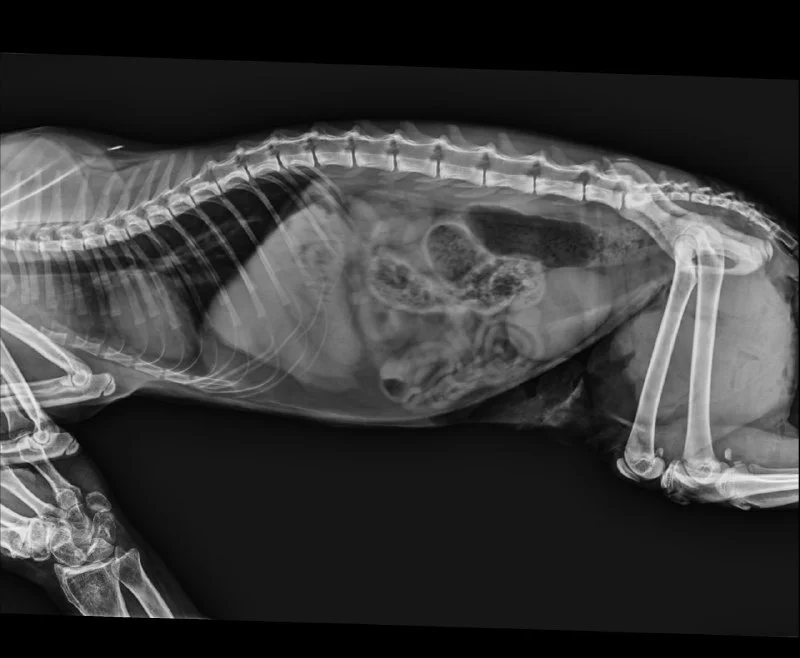

Подскажите, пожалуйста, кто может грамотно вылечить пневмонию у собаки или к кому можно срочно обратиться за вторым мнением (пульмонолог / терапевт)?

У собаки пневмония.

Уже 8 дней лечение Далацином и Фенофлоксом. На фоне терапии были улучшения. Лечимся в SMALL ANIMAL у Анастасии.

Изначально была гипоксия, 6 дней находился в кислородной камере.

После стабилизации начали постепенно выписывать домой, но мы ежедневно приезжаем на процедуры:

- ингаляции Пульмикорт + физраствор

- внутривенные антибиотики, стоит катетер

Раз в два дня делали рентген - динамика была нормальная, пошли бронхи.

Но вчера же появился сухой, непродуктивный кашель.

Вечером отдали его на процедуры, там вкололи Лазикс 0,25 от 1.7 ml (при весе 1,7 кг).

После процедур его вернули с синим языком, снова началась гипоксия, и его срочно поместили обратно в кислородную камеру.

Пока мы ждали его с процедур, слышали сильный крик. Есть подозрение, что антибиотик могли вколоть внутримышечно, и он сильно перенервничал.

Врачи утверждают, что всё вводилось через катетер, но на этой неделе уже был случай, когда при установленном катетере антибиотик в спешке сделали внутримышечно и он также кричал и перенервничал.

Сейчас он снова в кислородной камере, днём планируют повторный рентген.